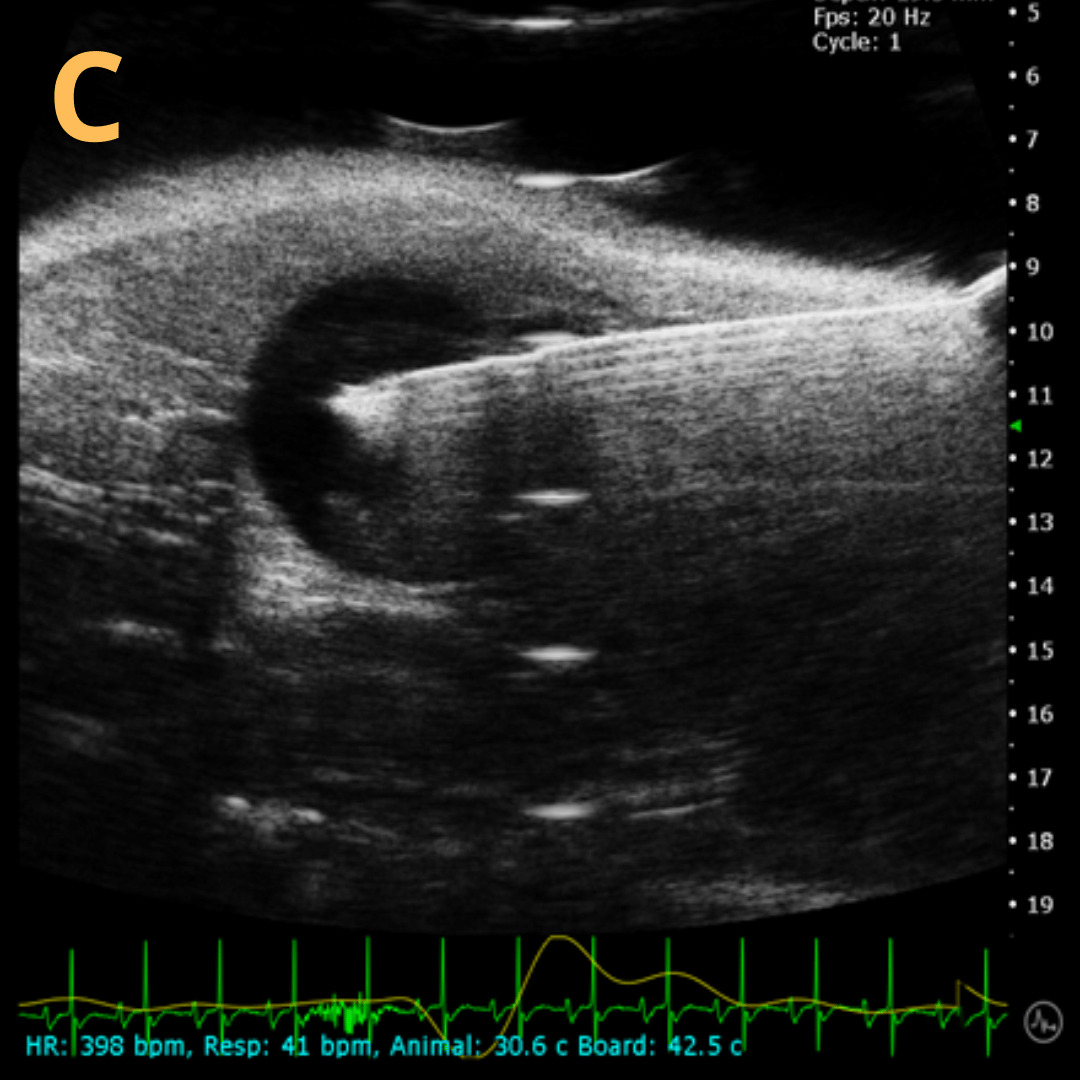

Ultrasound-Guided Injection

This is A) a B-mode video showing an injection into the bladder with B – D being still frames of B) before injection of any solution with the landmarks noted, C) during injection with bladder becoming notably larger, and D) the end of injection before needle will be removed. Imaging on a wildtype C57B6J mouse model – acquired images are from Stephen Zderic’s lab at the Children’s Hospital of Philadelphia.